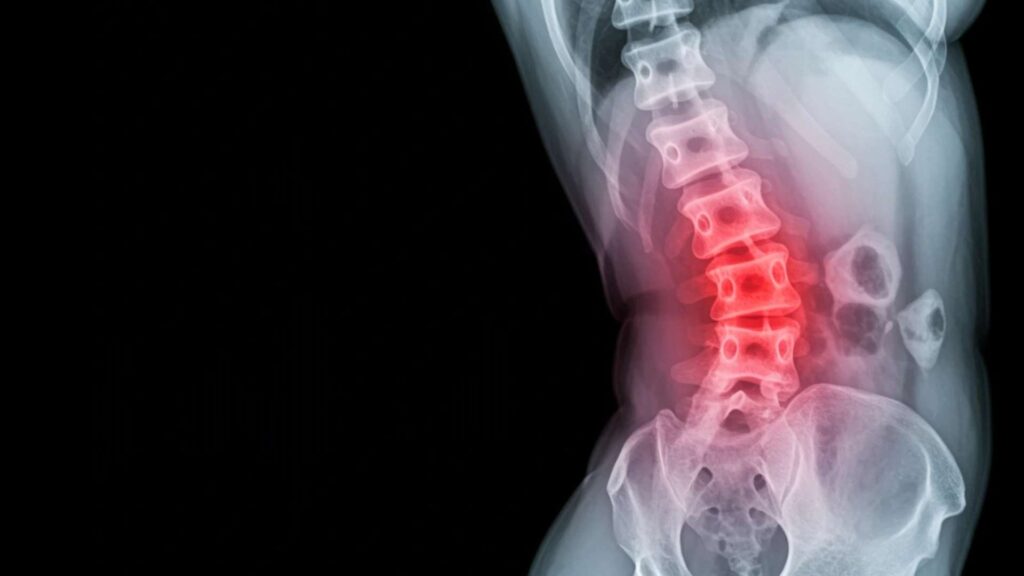

Radiographic Imaging

Radiographic imaging of joints is used to diagnose the progression of ankylosing spondylitis, assess the morphology of the joints, evaluate bone density, and detect changes around the joints. It includes X-rays and magnetic resonance imaging (MRI).

Imaging by X-rays is less sensitive than MRI, but it provides a general overview of the disease condition and any deformity in the spine. It is typically used to monitor disease progression in affected joints.